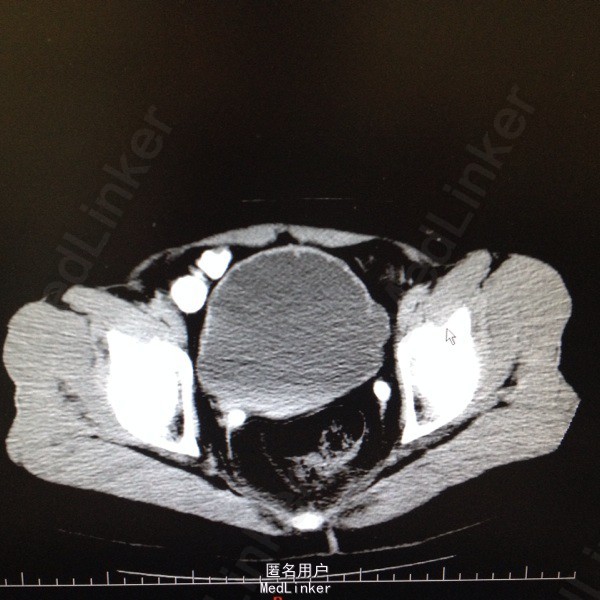

47岁女患。 病史:患者6年前因宫颈癌行全子宫及双侧附件切除。盆腔淋巴结清扫。腹主动脉旁淋巴结活检术。后又行局部放疗。因双肾积水来我科。患者自述平时轻微排尿困难,尿线细。

双肾区无叩击痛,双输尿管走形区无压痛。耻骨上区隆起,叩诊浊音。排尿后留置尿管引流尿液400ml。 辅助检查:肌酐99。 ct:双肾及输尿管积水。 留置尿管后一周泌尿系彩超:双肾积水明显减轻。具体见图片。

诊断:双肾及双输尿管积水 神经源性膀胱 给予患者留置尿管后1周行泌尿系彩超检查肾积水减轻。

宫颈癌根治及放疗后双肾积水情况较多见,常因输尿管壁内段狭窄或神经源性膀胱引起。此患者留置尿管后肾积水明显减轻。建议患者继续留置尿管或间断家庭导尿治疗。